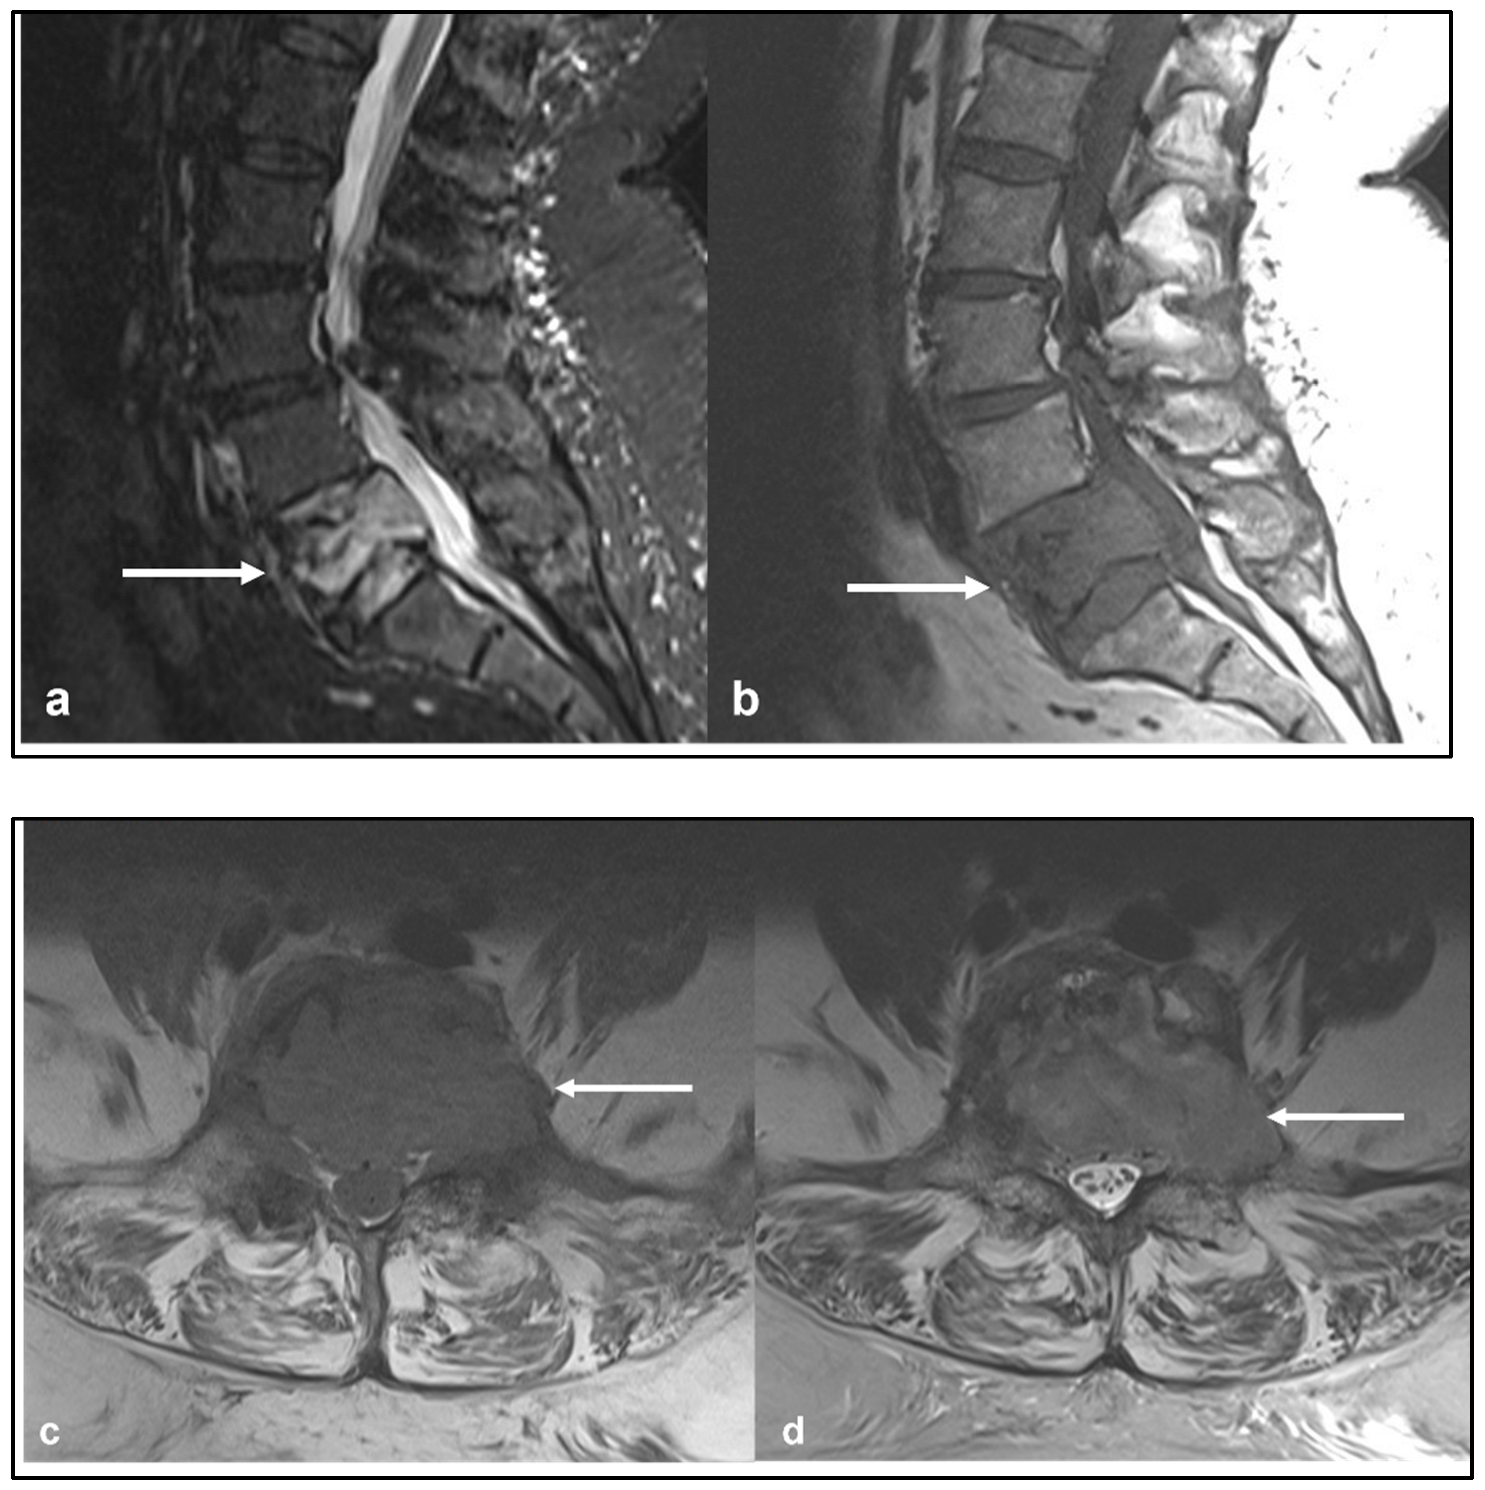

| Ewing sarcoma | Lytic lesion. Vertebral collapse. | Low to intermediate signal T1 and intermediate to high signal T2 lesion. Enhancing extra-osseous soft tissue component. |